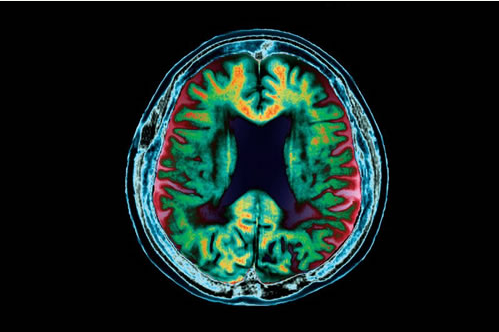

图片来源:Zephyr/SPL

你是否会患上阿尔茨海默氏症?关于该疾病或许能通过输血和手术设备扩散的恐惧一直在增长,但很难找到这种情况正在发生的证据。如今,一项发表于《分子精神病学》杂志的研究发现,一种阿尔茨海默氏症蛋白能在共享血液供给的小鼠间扩散并且导致大脑退化。